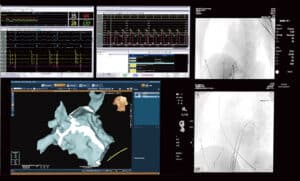

Dijital Anjiyografi Sistemi

Yapay zeka sinir ağı algoritmaları kullanılarak görüntü SNR’si iyileştirilirken bu arada doz azaltılır.

Zengin görüntüleme fonksiyonları doktorların cerrahi verimliliği artırmasına yardımcı olur.

Çeşitli pozisyonlara hızlı ve esnek hareket.

Lezyonlarda hızlı ve akıllı hedefleme.

Göğüs ve karın üzerinde C-kol baş tarafı pozisyonunda girişimsel operasyonla tanışın.

Zemin raylarında 97 cm hareket edebilen Cath-tablosu, geniş cerrahi kapsama alanı ve CPR pozisyonuna hızlı hareket etmeyi sağlar.